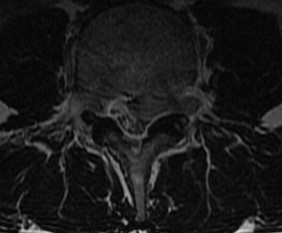

MRI

T2 Sagittal - myelogram

T1 Axial - see nerve root against white fat

MRI changes

1. Central root clumping

2. Empty sac appearance

3. Soft tissue mass in subarachnoid space